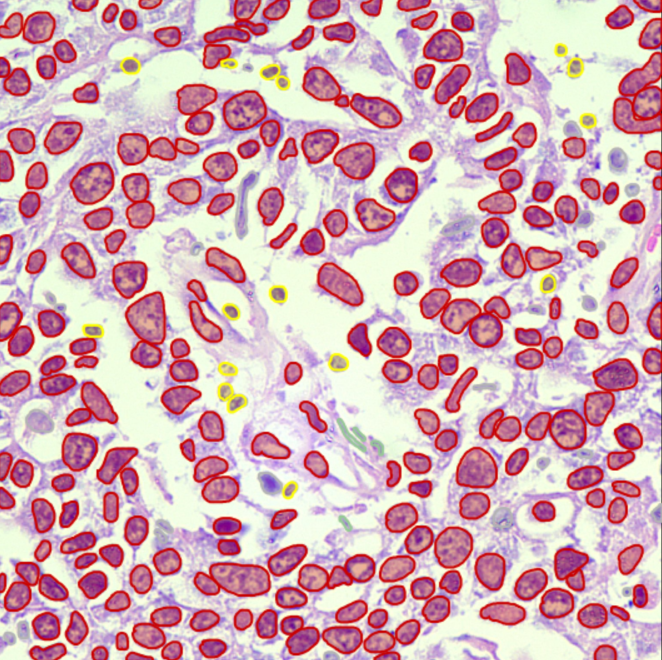

Cellular & Structure Level

High-precision single-cell annotation, mitotic figures, nuclear/cytoplasmic contours, and structure-level tagging.